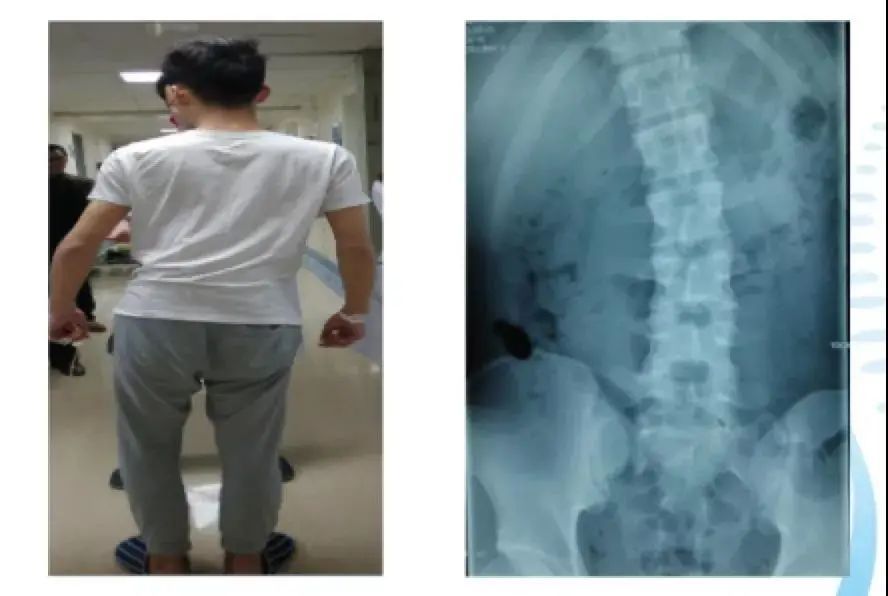

你能想象吗?这是一位16岁青少年的脊椎,它因疼痛而发生变形,侧弯程度严重到肉眼可见。

这个16岁的男孩叫小涛,正读高中。有天,他正在篮球场上“旋转跳跃”,突然腰部传来一阵剧痛……

父母急忙送小涛去医院,小涛的情况并不乐观,病情已经不能再拖延,医生紧急给他安排了经皮脊柱内镜微创手术。

据接诊的医生说,小涛“来的时候,已经有了非常明显的代偿性脊柱侧弯”。

原来,小涛平时因为上课经常久坐,晚上也常常熬夜,“长期的久坐导致腰椎间盘已经有了损伤,埋下隐患,再加上打篮球这样的剧烈运动所产生的外力,从而诱发了疾病。”